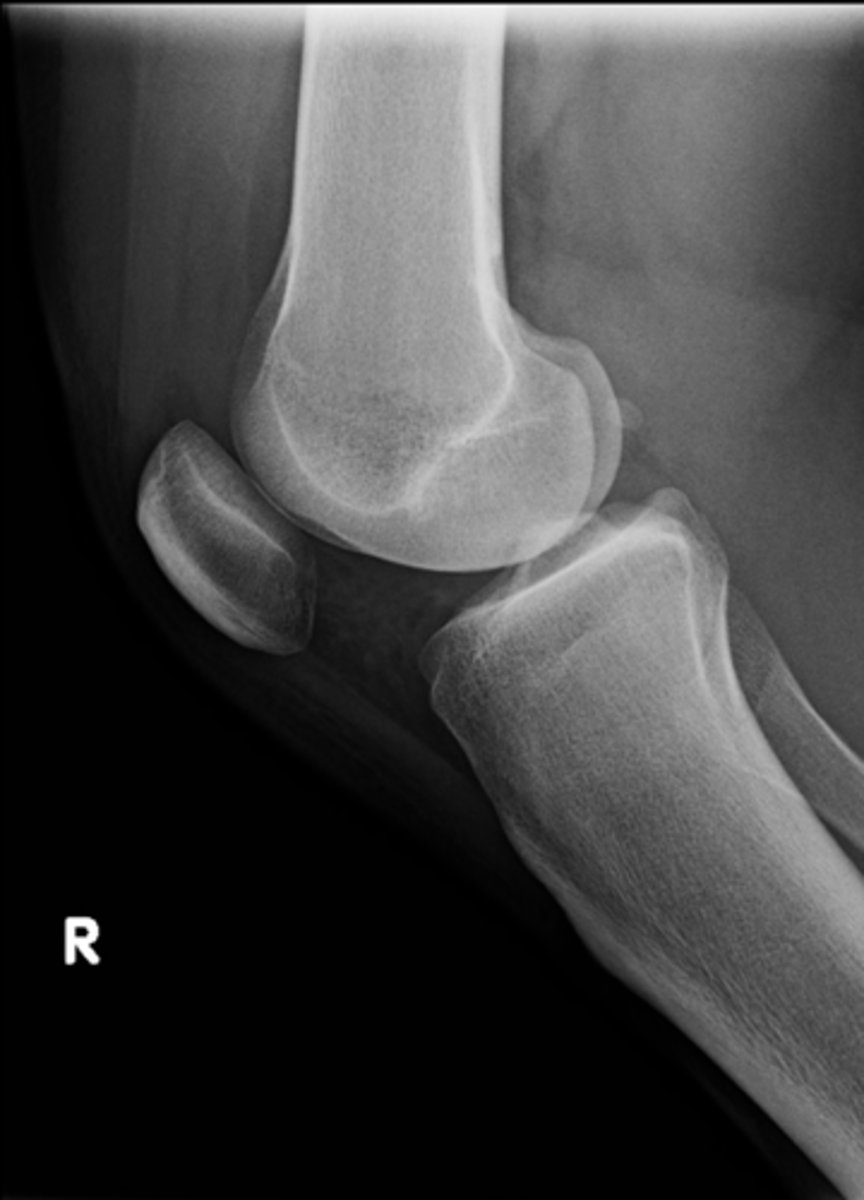

Lateral knee

ID standard knee projection

Flexion

Ludloff's patch/spot

- Not a true anatomical structure

- Appears due to less bone being traversed anteriorly than posteriorly